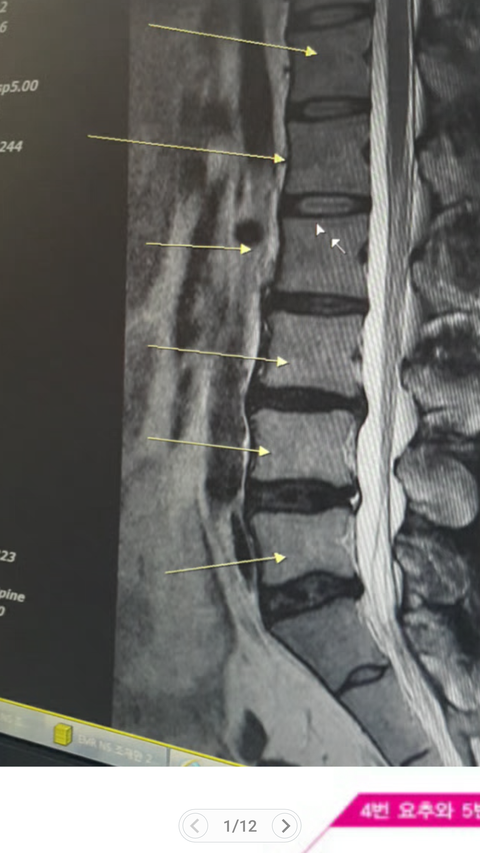

★ 첫번째 입원 : mri 검사상 요추 3 - 4 - 5(3번은 퇴행) 천추 1번 추간판 변성 팽륜, 요추 염좌 / 다발성이긴 하나 디스크 돌출이 많이 된 상태는 아님

★ 두번째 입원 : ct검사상 요추 3 - 4 - 5(3번은 퇴행) 천추 1번 추간판 팽륜 변성, 요추 염좌 및 근근막 통증 증후군 / 디스크는 돌출이나 악화되지 않은 상태